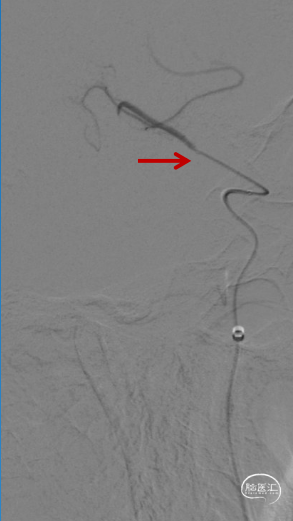

交换出微导管及多功能导管,C2段放置SPIDER保护伞后以3-30mm球囊和6F 115cm SKATHI远端通路导管采用球囊接力技术越过颈内动脉闭塞段,由下及上持续抽吸。

3. 对于串联病变中来讲,越过闭塞段抵达颈内动脉远端是第一步,像本例患者由于缺乏着力点并且C1段斑块较硬,微导管微导丝难以奏效。利用多功能管的头部弯曲对准闭塞段,采取较硬的微导丝如Command或者PT能有效突破闭塞段,在跟进中间导管时采用球囊接力技术不但可以轻松越过闭塞段,而且可以防止损伤中间导管(或抽吸导管)头端,避免头端损伤后抽吸能力下降。